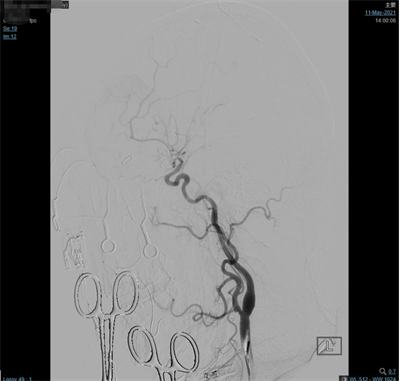

夹闭前造影

患者气管插管全麻满意后,双侧腹股沟区常规消毒铺巾,右侧腹股沟韧带下方股动脉搏动最强点下方约1.5cm处穿刺,右股动脉行Seldinger穿刺,置入5F动脉鞘,超滑泥鳅导丝携带5F单弯造影管分别行双侧颈总动脉、双侧颈外动脉及双侧椎动脉正侧位造影,造影见:右侧大脑中动脉M1分叉处2个动脉瘤;左侧大脑中动脉M1分叉处2个动脉瘤,其中一个可见子瘤。仰卧位头右偏。常规碘酒及酒精消毒后铺巾。取左额颞弧形切口,逐层切开头皮及皮下,切开颞肌筋膜及颞肌,筋膜下入路,颞肌翻向下方,暴露颅骨。颅骨钻1孔,铣刀铣下骨瓣约5X3cm大小。硬膜张力不高。分离蝶骨嵴两侧硬脑膜,进一步咬除蝶骨嵴。硬膜四周悬吊。弧形剪开硬脑膜,向前翻转固定。显微镜下锐性分离侧裂,打开蛛网膜,放出脑脊液后脑组织压力下降,显露颈内动脉,大脑中动脉及其分支,见动脉瘤位于大脑中动脉M1段。分离动脉瘤两侧粘连蛛网膜,显露动脉瘤前后端中动脉及其分支,分离瘤蒂两侧,上1枚临时阻断夹阻断左侧大脑中动脉,后更换另1枚临时阻断夹阻断左侧大脑中动脉,上3枚德国进口动脉瘤夹夹闭2个动脉瘤瘤蒂,调整后夹闭满意,松阻断夹,术中动脉瘤未破裂。造影显示中动脉及其分支通畅。创面止血,覆盖止血纤维及凝血酶海绵,生理盐水冲洗清亮,脑组织搏动良好。护士清点棉条、棉片、纱布及器械无误,严密缝合硬膜。骨瓣复位,3枚钛片固定。逐层缝合颞肌、颞肌筋膜、皮下及头皮各层。包扎固定纱布,酒精消毒术前贴膜,将患者头左偏,取右额颞弧形切口,逐层切开头皮及皮下,切开颞肌筋膜及颞肌,筋膜下入路,颞肌翻向下方,暴露颅骨。颅骨钻2孔,铣刀铣下骨瓣约5X5cm大小。硬膜张力不高。分离蝶骨嵴两侧硬脑膜,进一步咬除蝶骨嵴。硬膜四周悬吊。弧形剪开硬脑膜,向前翻转固定。显微镜下锐性分离侧裂,打开蛛网膜,放出脑脊液后脑组织压力下降,显露大脑中动脉及其分支,见动脉瘤位于大脑中动脉M1段,分离动脉瘤两侧粘连蛛网膜,显露动脉瘤前后端中动脉及其分支,分离瘤蒂两侧,第3枚临时阻断夹阻断右侧大脑中动脉上一枚德国进口动脉瘤夹夹闭瘤蒂,调试后夹闭满意,松阻断夹,术中动脉瘤未破裂。造影显示中动脉及其分支通畅。创面止血,覆盖止血纤维及凝血酶海绵,生理盐水冲洗清亮,脑组织搏动良好。护士清点棉条、棉片、纱布及器械无误,严密缝合硬膜。骨瓣复位,3枚钛片固定。逐层缝合颞肌、颞肌筋膜、皮下及头皮各层。手术顺利,术中出血约700ml,回输自体血140ml。手术时间较长,患者带气管插管安返神经外科-ICU病房。